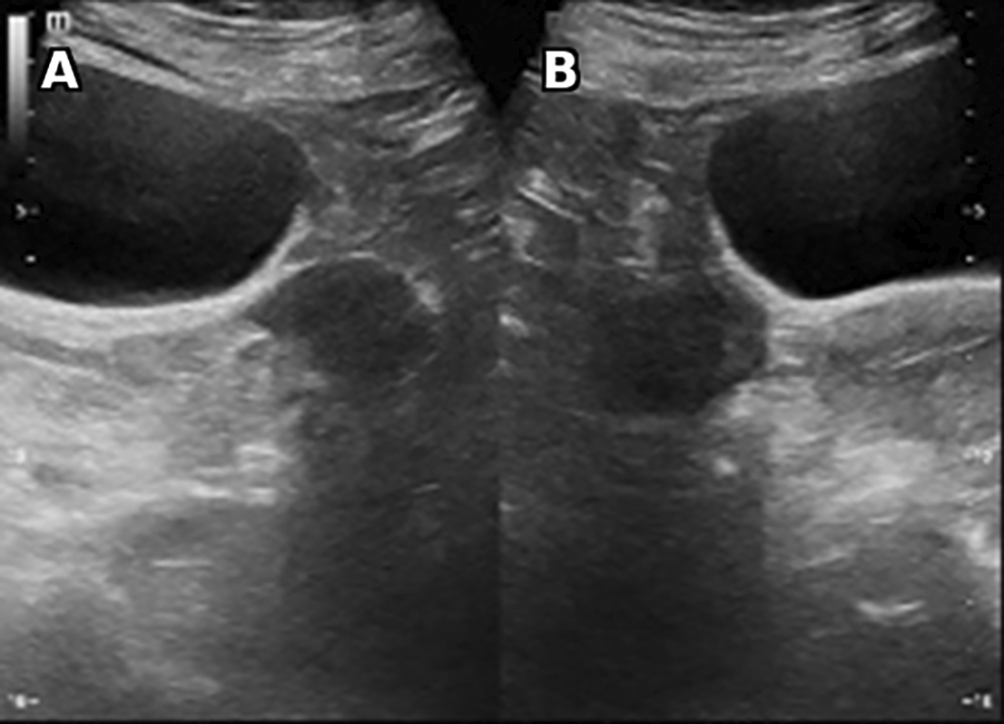

Laboratory studies revealed very high testosterone levels at 4.7 nmol/l, rechecked several times (N:0.2-3.5 nmol/l), normal levels of CA 125, DHEA-S and normal corticotropic balance with good dexamethasone control. A pelvic ultrasound was performed showing bilateral well defined hypoechoic round solid ovarian masses ( Figure 2).

Vascularity is noted (not shown). No calcification, ascites or retroperitoneal lymphadenopathy were found.